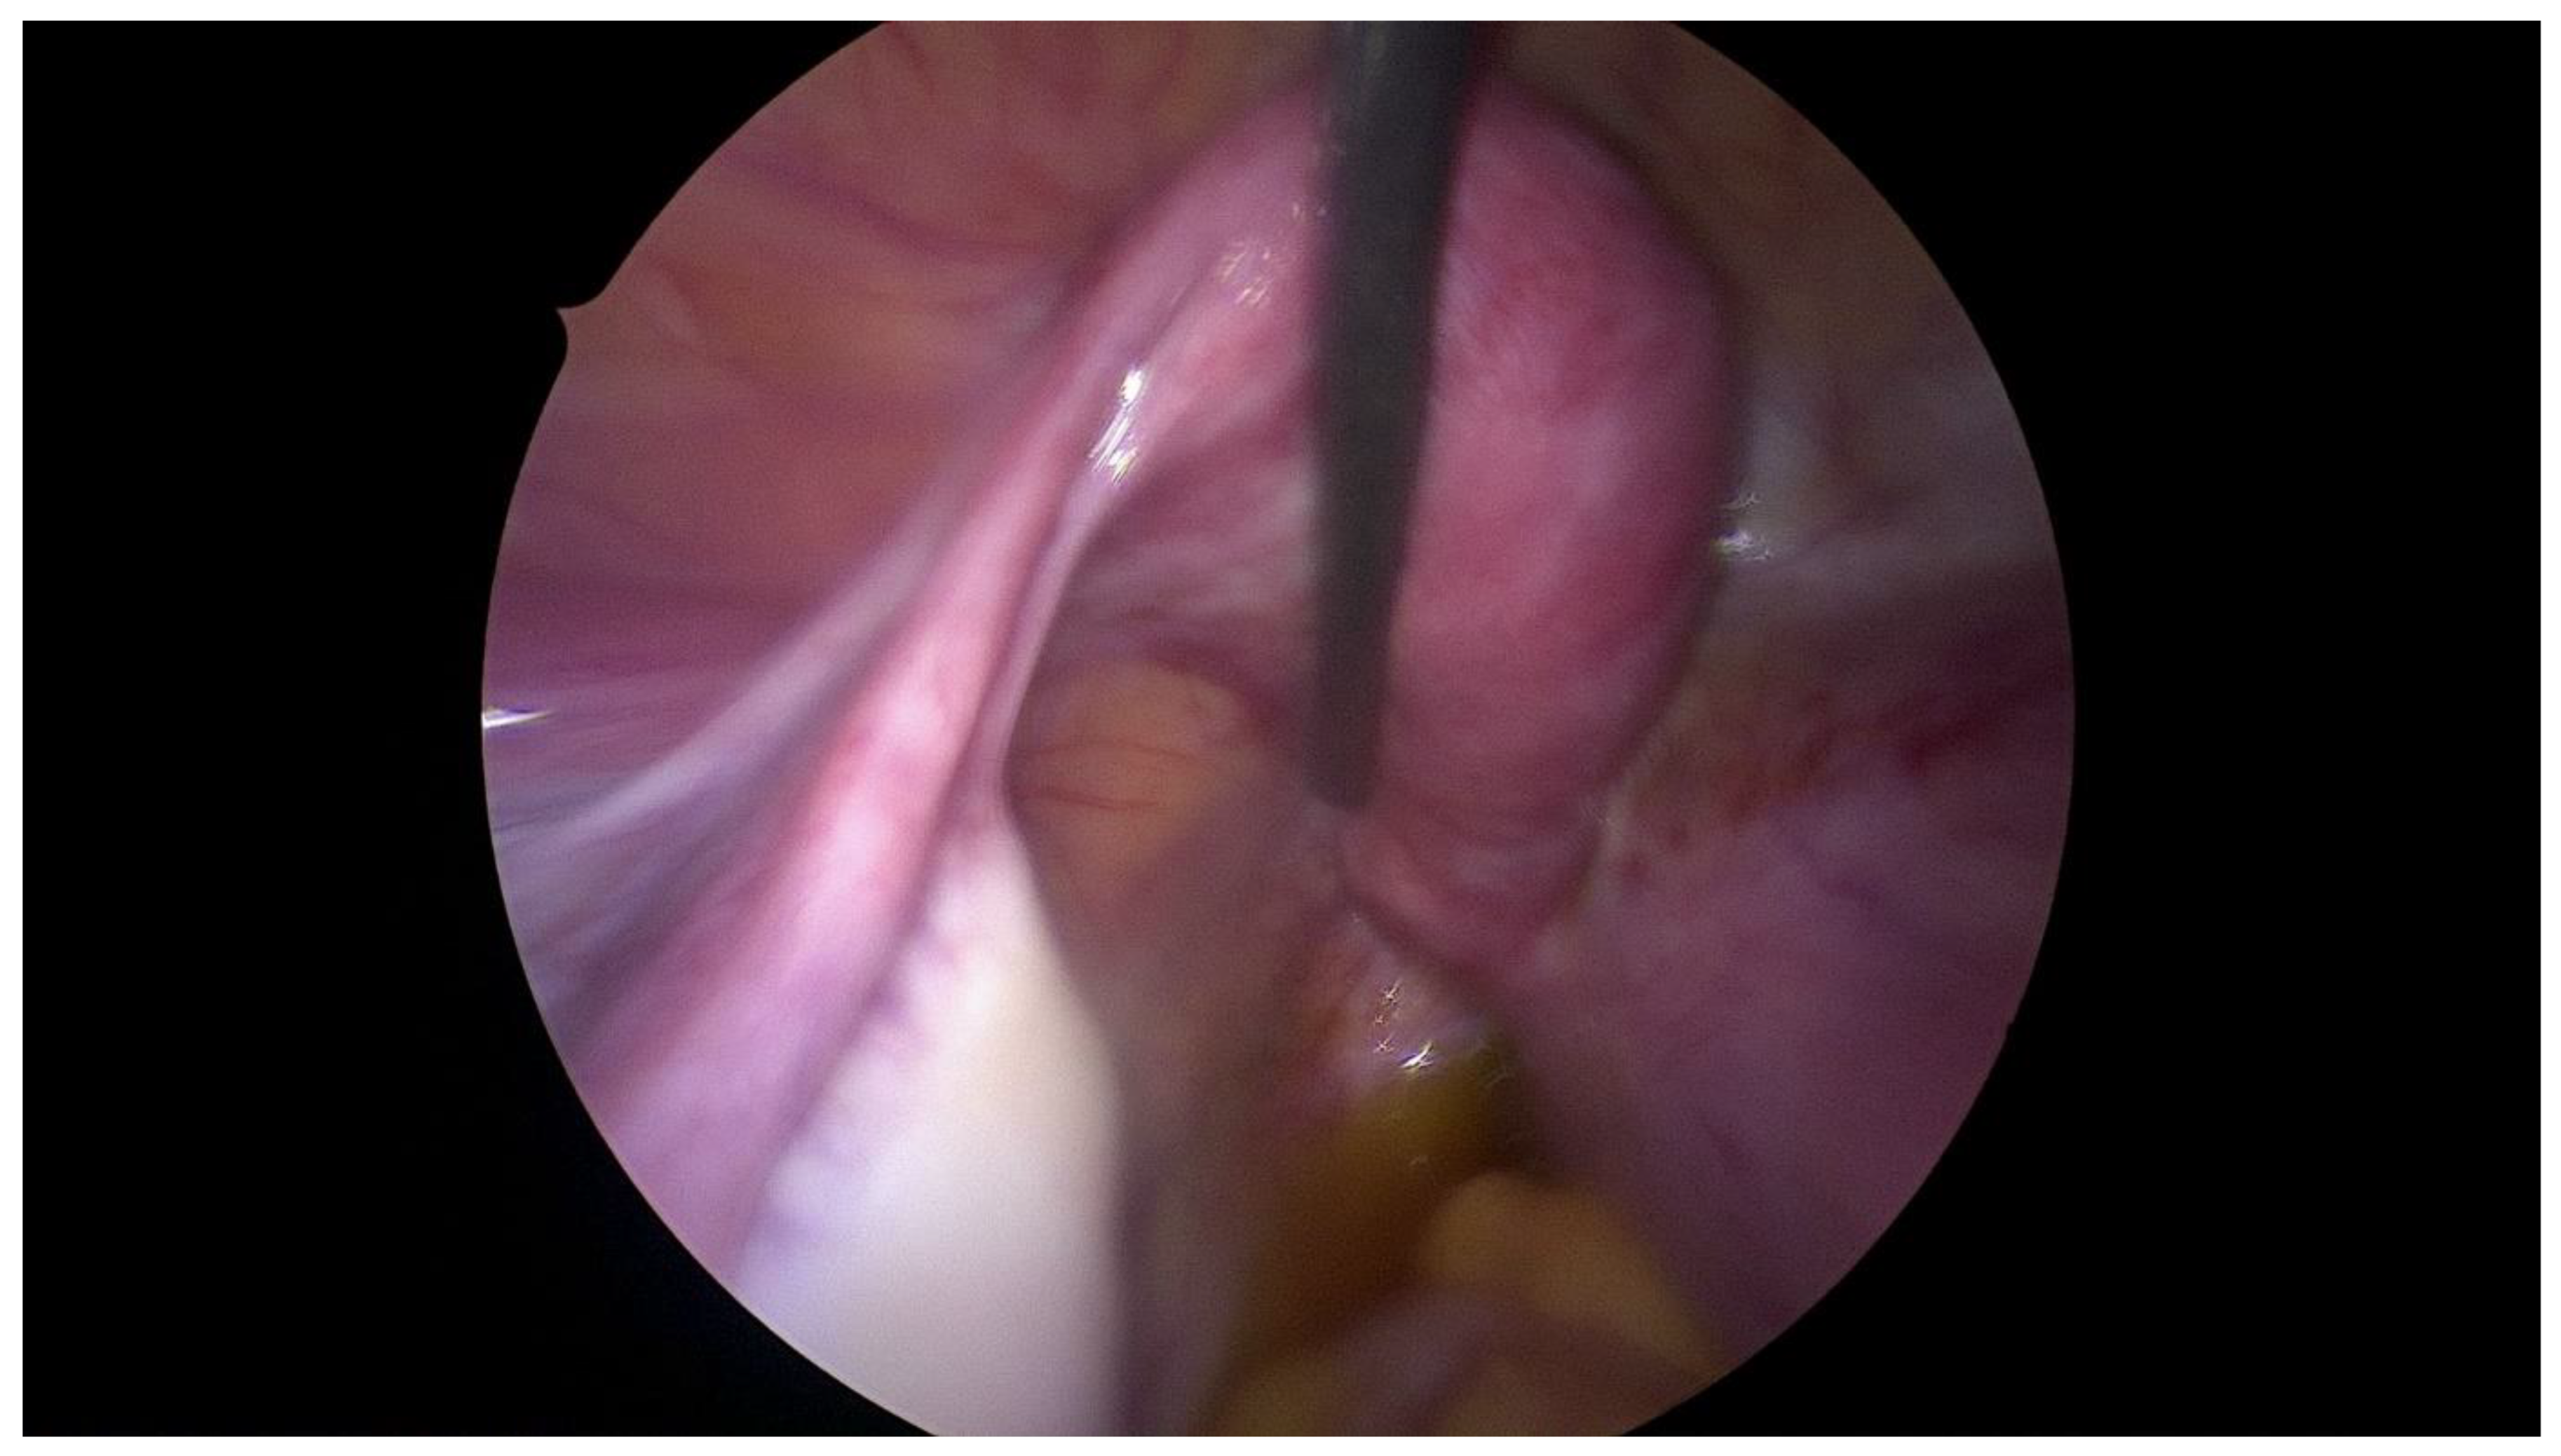

Step 3 Surgical management Surgery is necessary when acute abdominal symptoms are present. “Wait and see” approach is only possible when the clinical situation allows it. Perform laparoscopy and vaginoscopy in order to achieve the correct diagnosis and treat concomitant hematosalpinx and endometriosis [14]. Intraoperative US is helpful to evaluate the place of resection. Unnecessary lengthening the time to diagnosis, contributes to unindentent consequence. |

Step 4 Postoperative management The insertion of uterine catheter filled with saline into a place of stenosis allow to avoid the risk of possible restenosis [15]. Continuous oral contraceptives are recommended to avoid possible consequences like the risk of restenosis. |